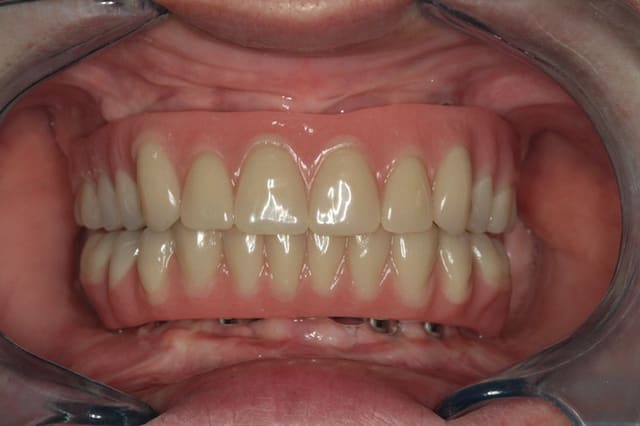

Voilà les photos de la nouvelle résine. (Malheureusement Posit, je n'en avais pas fait avant démontage)

C'est la 2ème fois que l'on renouvelle la résine. Pour le reste : armatures, piliers, vis : tout a 21 ans ! La patiente m'a dit que 2 ou 3 fois une dent s'est décollée.

C'est quand même un cas assez exceptionnel parce que l'hygiène n'est pas tip top, et les contrôles très irrégulier.